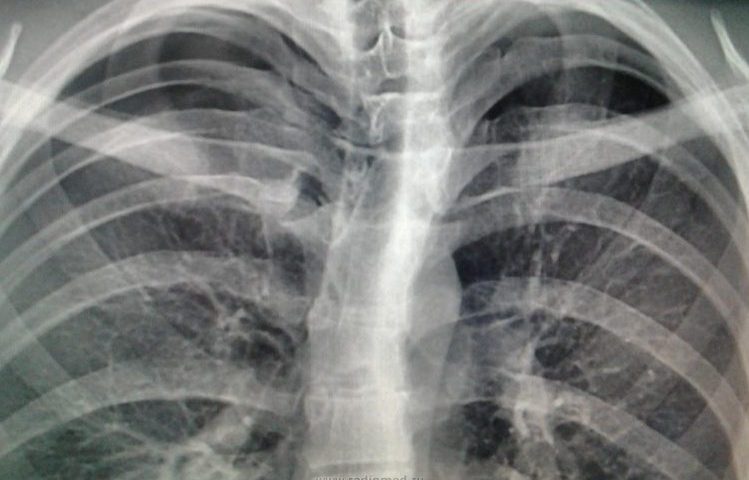

Апікальний пневмоторакс — що це таке?

Апікальний (розташований у верхній частині) пневмоторакс являє собою порушення руху …